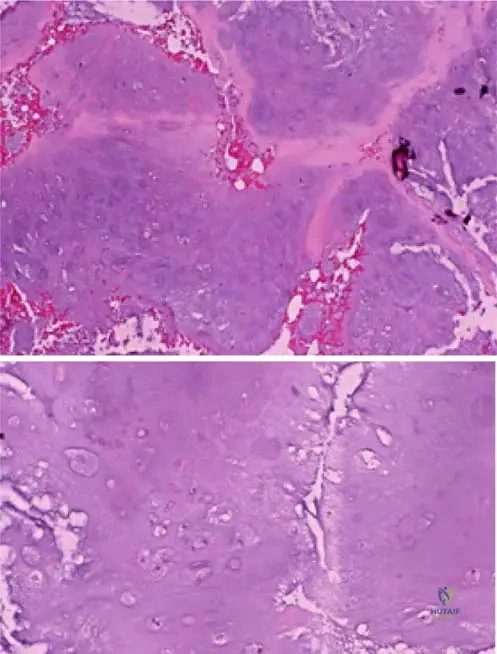

A 32-year-old male has a biopsy of a juxtacortical cartilaginous lesion. Histopathological examination is performed.

View Answer & Explanation

Correct Answer: B

Rationale: Fig. 8.28 and its description indicate that "Periosteal chondromas are typically more cellular than their intramedullary counterparts." This increased cellularity is a key distinguishing feature.

A 29-year-old female presents with a palpable mass on her humerus. Imaging shows a well-defined cartilaginous lesion arising from the periosteum. Histological examination is performed.

Correct Answer: C

Rationale: Fig. 8.29 and its caption state that periosteal chondromas "often display a lobular growth pattern." This is a characteristic histological feature.